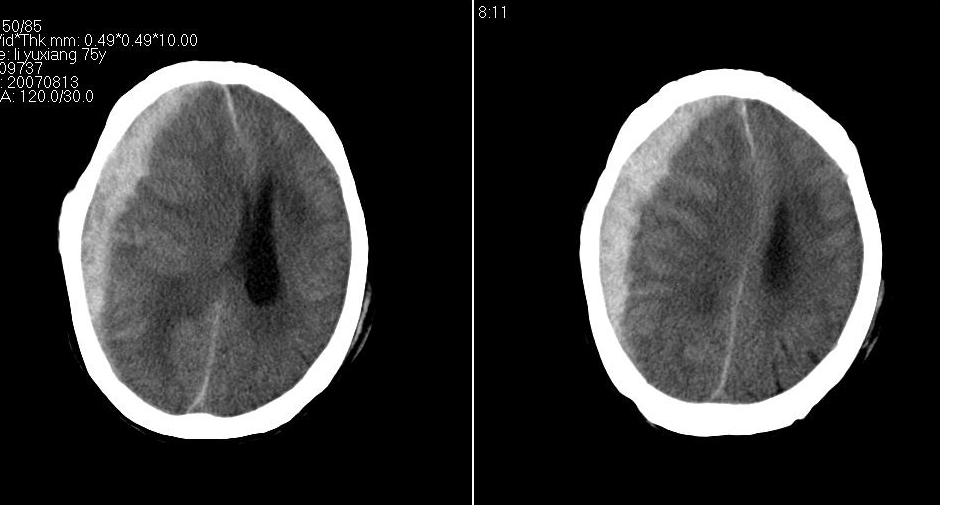

以下是引用川北影像在2007-8-14 15:33:00的发言:[br]1、右侧颞叶脑挫裂伤伴血肿形成。[br]2、右侧额颞顶部硬膜下血肿伴大脑廉下疝形成。

以下是引用gaoshengjiang在2007-8-14 16:30:00的发言:[br]大家都认为右侧颞叶脑挫裂伤伴血肿形成;右侧额颞顶部硬膜下血肿伴大脑廉下疝形成;蛛网膜下腔出血。 但硬膜下血肿、脑内血肿量不多,而大脑廉下疝明显,右侧颞叶类圆形高密度灶,周围轻度水肿,呈蟹足状,考虑脑内占位所致脑内血肿、突然晕倒、硬膜下血肿、颞叶脑挫裂伤等一系列改变。[br][br] [br]

以下是引用拾荒者在2007-8-14 21:59:00的发言:[br][quote]以下是引用gaoshengjiang在2007-8-14 16:30:00的发言:[br]大家都认为右侧颞叶脑挫裂伤伴血肿形成;右侧额颞顶部硬膜下血肿伴大脑廉下疝形成;蛛网膜下腔出血。 但硬膜下血肿、脑内血肿量不多,而大脑廉下疝明显,右侧颞叶类圆形高密度灶,周围轻度水肿,呈蟹足状,考虑脑内占位所致脑内血肿、突然晕倒、硬膜下血肿、颞叶脑挫裂伤等一系列改变。[br][br] [br]